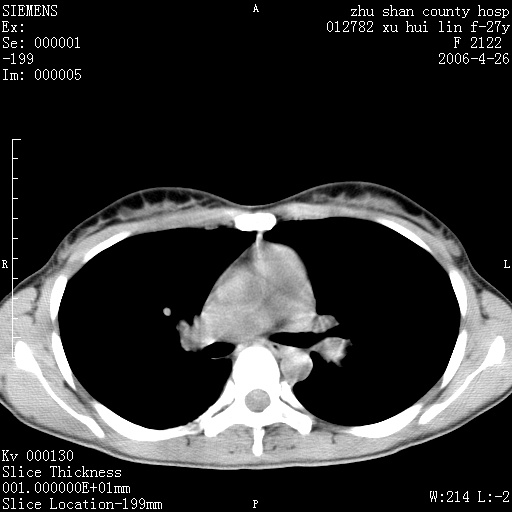

女性 病人 27岁!本院职工家属,五月前因感冒透视发现病变,ct示:左肺下叶背段感染性病变。经过半月规范抗生素治疗后复查病变无明显变化,后行四月规范抗痨治疗,复查无明显变化,后复查无效!请大家帮忙看看!

右肺下叶背段见片状高密度区,边界不清,密度不均,无钙化及空洞影,背段支气管通畅。所见层面肺门及纵隔内未见明显肿大淋巴结影。

女性 病人 27岁!本院职工家属,五月前因感冒透视发现病变,ct示:左肺下叶背段感染性病变。经过半月规范抗生素治疗后复查病变无明显变化,后行四月规范抗痨治疗,复查无明显变化,后复查无效!

诊断:首先还是考虑为慢性炎症。

结核虽然好发于下叶背段,但周围无明显卫星灶,化验结果怎样?